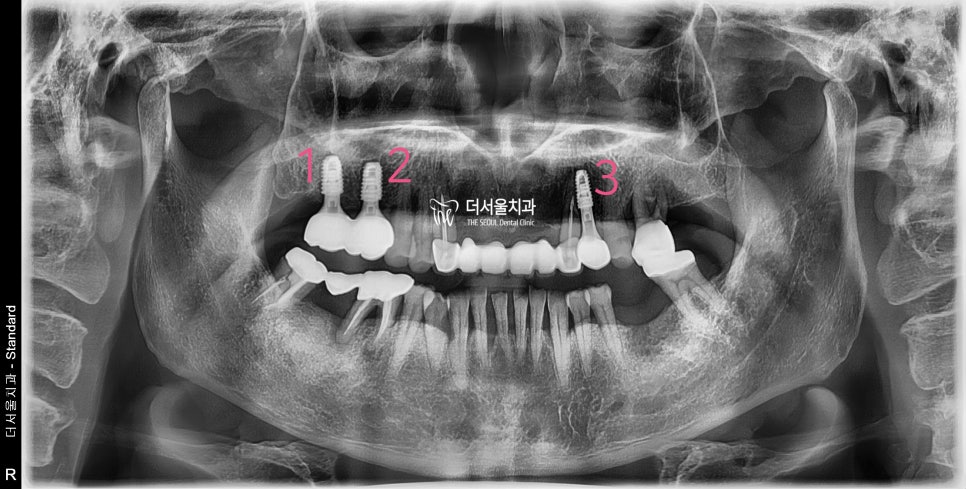

『최종 결과』

앞서 설명드린

네비게이션 임플란트 가 가질 수 있는

이점에 따라서 소수술을 진행했습니다.

최소 내원 횟수로 치과에 내원을 하셨으며

수술이 끝났음에도 통증이나 붓기는

거의 없다고 직접 환자께서 말씀을 하셨습니다.

그렇게 좋아하셨던 모습은,

또 오랜만에 보긴 했었네요.

어금니 결손에 따라서 비어있던 공간은,

네비게이션 임플란트 의 도움을 받아서

새로운 치아가 탄생 될 수 있었습니다.

이제는, 식사만 맛있게 하면 되겠군요.^^